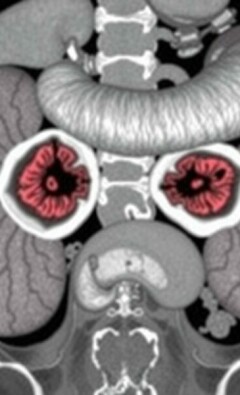

Diferencia entre apendicitis y diverticulitis: cómo reconocer, diagnosticar y tratar dos causas comunes de dolor abdominal